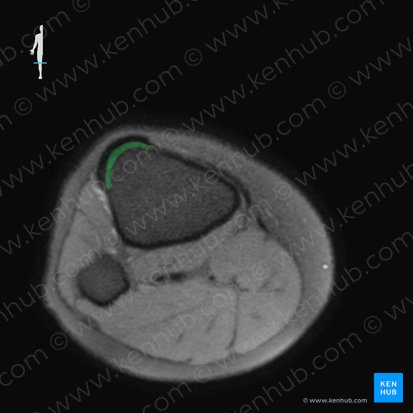

La tuberosidad tibial es una gran protuberancia ancha ubicada en la cara anterior de la tibia proximal.

Esta estructura puede ser palpada fácilmente como la protuberancia que está situada justo inferior a la patela. Superior a la tuberosidad tibial se encuentra la bursa subcutánea infrapatelar.

La tuberosidad tibial proporciona la inserción inferior para el ligamento patelar, también conocido como el ligamento rotuliano o el tendón común del cuádriceps.

Definición | Gran protuberancia ósea en la cara anterior de la tibia proximal |

Función | Punto de inserción para el ligamento patelar |